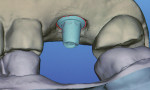

The Cadent iTero 4.0 digital impression system is physically similar to the Lava C.O.S. in that it consists of a handpiece wand attached via a cable to the CPU cart with a flatscreen monitor (albeit not a touchscreen monitor). The iTero scanning wand is physically larger and heavier. This is in part because the iTero wand uniquely emits a gentle stream of compressed air to keep the lens surface from fogging. The wand features parallel confocal imaging using laser and optical scanning to capture the surface detail of the intraoral hard- and soft-tissue structures. iTero’s specific parallel confocal scanning captures the image data to an accuracy of 15 µm at focal depth intervals of 50 µm. This is accomplished with no powder being placed on the highly reflective surfaces characteristically found on enamel, polished or glazed porcelain, ceramic, and metallic restorations. The technology also allows contact scanning with the disposable wand sheath touching directly against oral tissues, and has the ability to scan subgingivally since there is no risk of powder being smeared on the lens. Simply put, if the operator can see the finish line in a relatively dry field under the tissue, it can be recorded. This technology has proved to be accurate for scanning four- to five-unit fixed partial dentures with multiple pontic spans.4

The sequence of scanning with the iTero is similar to the Lava C.O.S. but the actual step-by-step technique differs. The Lava C.O.S. wand is glided above the surfaces of the powdered teeth in a continuous video-acquiring motion.5 The iTero scan is prompted by a software-generated verbal command instructing the operator to position the wand in an exact location to make a data snapshot. The software then knits together the overlapping snapshots through real-time modeling (RTM) to construct each arch occluded in the maximum intercuspation position (Figure 3). This sequence rapidly forms a real-time image on the monitor in 2 to 5 minutes, as the Lava C.O.S. does. With recently released updated software, RTM allows the operator to selectively erase an undesirable area from the file and rescan the data by section. This editing feature is an enhancement over the previous software wherein the quadrant or arch had to be totally rescanned. The highly defined RTM image enables the user to mark the preparation margin before sending the file to the laboratory. This is a great convenience because it potentially allows the dentist and laboratory to be less dependent on the iTero file reader’s expertise to identify the preparation finish line.